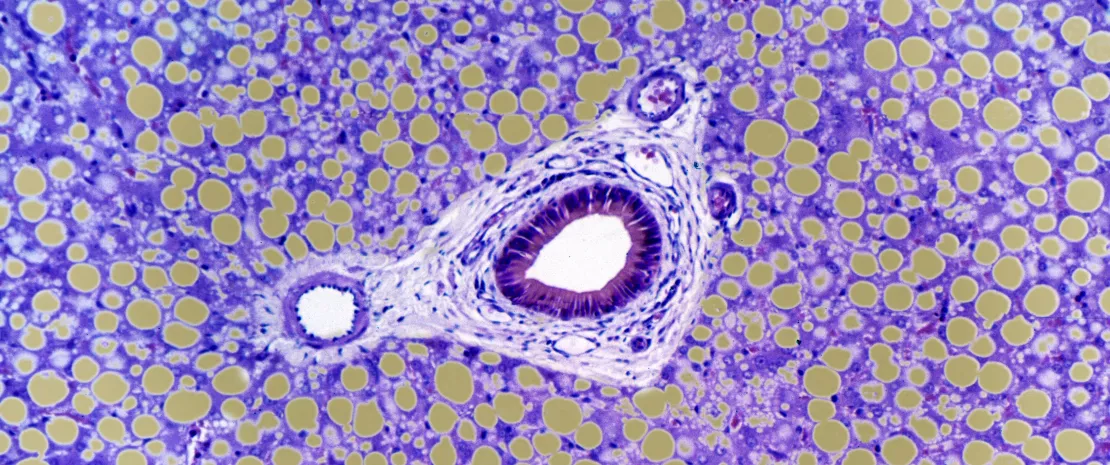

A doença hepática alcoólica está associada a uma elevada taxa de mortalidade e a poucas inovações terapêuticas e prognósticas. O papel da relação entre o intestino e o fígado foi recentemente evidenciado nas complicações do alcoolismo, especialmente através da translocação das bactérias intestinais para o fígado. Poderá a disbiose fúngica estar também envolvida?

Proliferação de Candida albicans

Com base numa coorte norte-americana e europeia, uma equipa internacional estudou a microbiota intestinal de 59 doentes com hepatite alcoólica, 15 doentes com problemas de consumo de álcool* (em diferentes fases de lesão hepática), bem como 11 indivíduos controlo. Observou-se uma clara proliferação de Cândida em ambos os grupos de doentes, bem como uma menor diversidade e quantidade de fungos em comparação com o grupo controlo, onde o Penicillium era dominante. Além disso, foi estabelecida uma correlação entre a microbiota intestinal e os parâmetros clínicos: a Candida foi associada a um aumento da fibrose pericelular, enquanto o Penicillium foi associado a uma redução da inflamação e diminuição dos corpos de Mallory**.